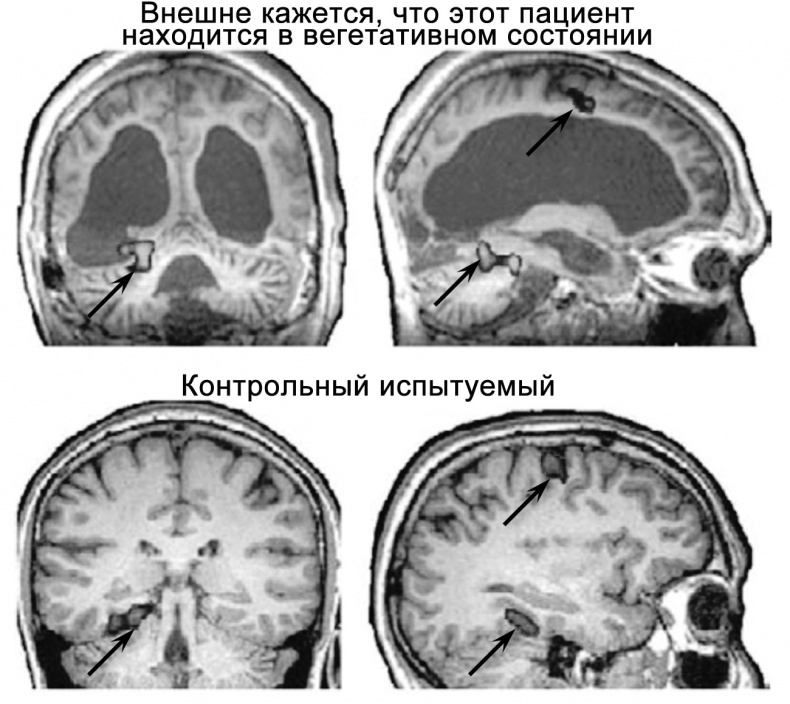

Рисунок 30. Некоторые пациенты, внешне демонстрирующие признаки вегетативного состояния, при выполнении сложных умственных задач показывают практически нормальную активность мозга, а следовательно, можно предположить, что они находятся в сознании. Пациент в верхней части рисунка не мог ни двигаться, ни говорить, однако корректно отвечал на заданные ему вопросы, активизируя для этого различные участки мозга. Чтобы ответить «нет», он должен был представить, будто входит к себе в квартиру, а «да» — вообразить, что играет в теннис. Когда пациента спросили, звали ли его отца Томас, участки мозга, отвечающие за пространственное ориентирование, активировались так же, как у здорового человека, то есть ответ (соответствующий действительности) был «нет». При этом пациент не демонстрировал никаких признаков способности к коммуникации, а также признаков сознания, и потому считалось, что он пребывает в вегетативном состоянии. На снимке хорошо видны имеющиеся у него обширные поражения мозга